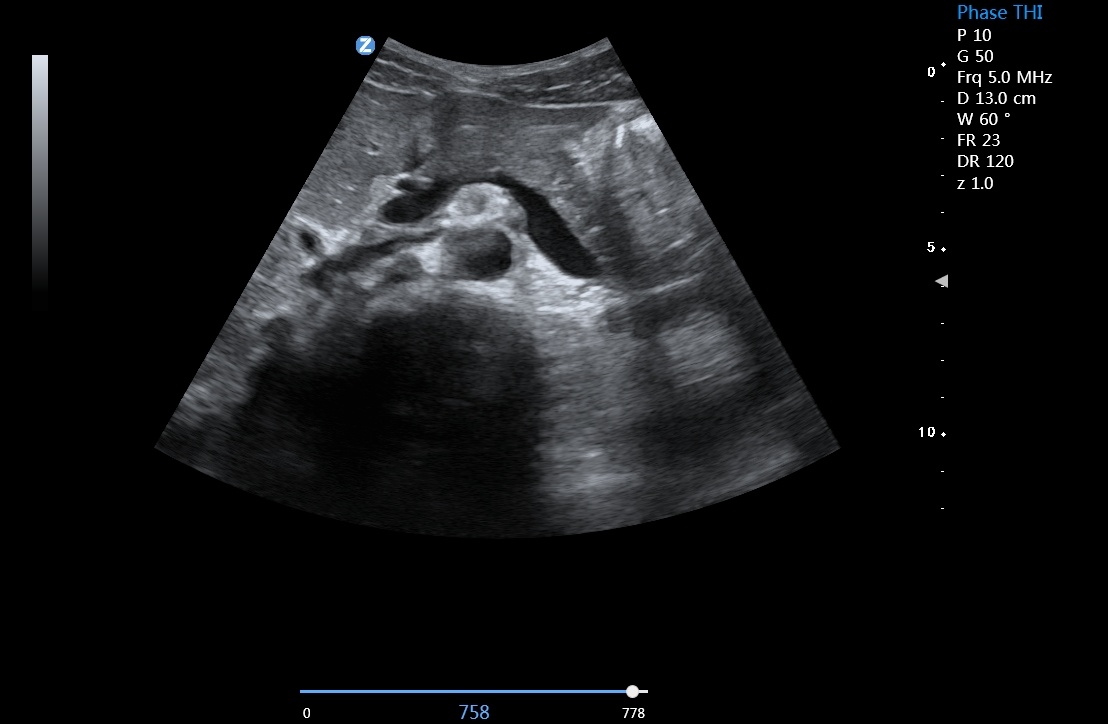

自适应空域滤波技术 zonClear

有效降低斑点噪声,大幅增强组织边界显示能力和组织回声显示能力

宽景成像

可提供更全面的扫查视野,为临床带来精准高效的疾病诊断

优异的临床图像